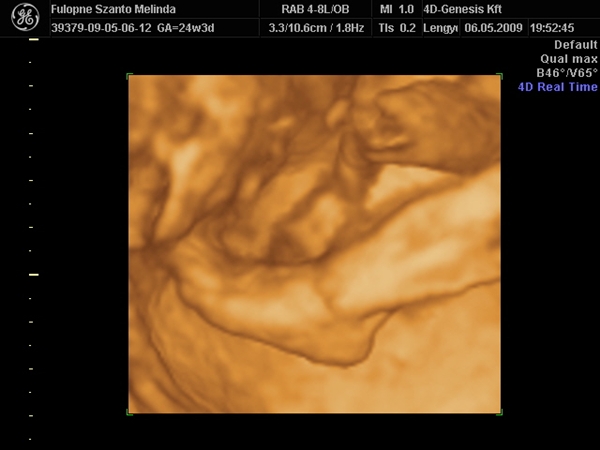

Na rakok képet,Budán voltunk a 4d genesis,de megmutatom,van honlapja.... Kép Kép Kép Kép Kép

Szóval!Nagyon csodálatos volt látni (nekem újra) a picúrt! :lol:

Mint ahogy kiderült,nem is olyan picúr!Ma vagyok 15 hét 2 napos,a bab méretei meg 16 hetesnek felel meg.Persze tudom,ez még változhat.Szegénykém olyan furi pózt vett fel,de hát ha neki úgy kényelmes,legyen úgy! :lol: :lol: :lol: :wink: Úgy képzeljétek el,mint a fordított C betű.Lent van a feje,felfelé áll a törzse és balra fordulva a lábai.Nem tudom elég érthető volt e így,de sajna jobban nem tudom elmagyarázni.

Átnézték a szívét( ok, meg van mind a 4üreg), a veséjét, az artériákat, vénákat, köldökzsinórt, megszámoltuk az ujjait. Kaptam képet is, 4D-set. Átkapcsolt 4Ds-re is.

Nagyon jól látszott minden! Én is tök jó láttam!

A lényeg, hogy minden ok! :-)